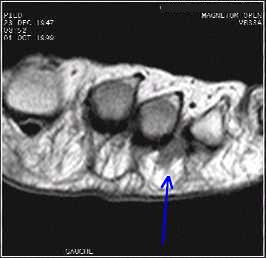

Musculosketal cases